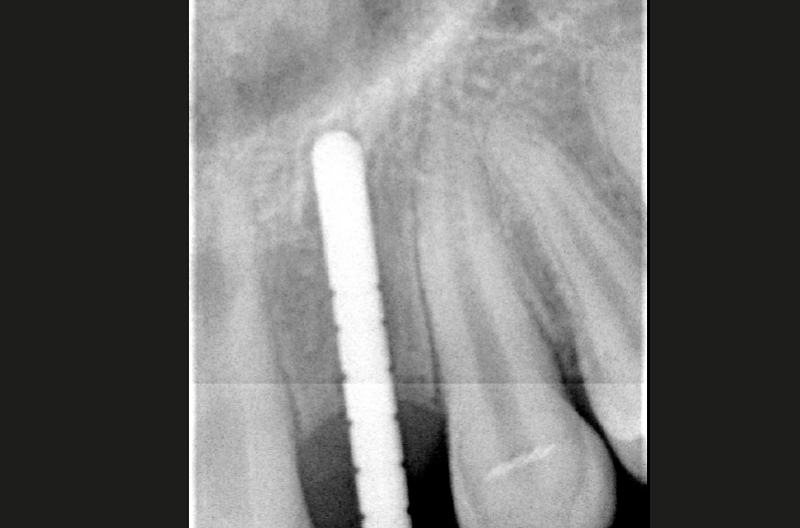

Depth gauge seated in the pilot hole to take an X-ray

X-ray to confirm proper distance to adjacent teeth

Control X-ray position #22 confirms correct placement of the implant, ExaConnect and the screw-retained crown

Control X-ray position #12 confirms correct placement of the implant, ExaConnect and the screw-retained crown